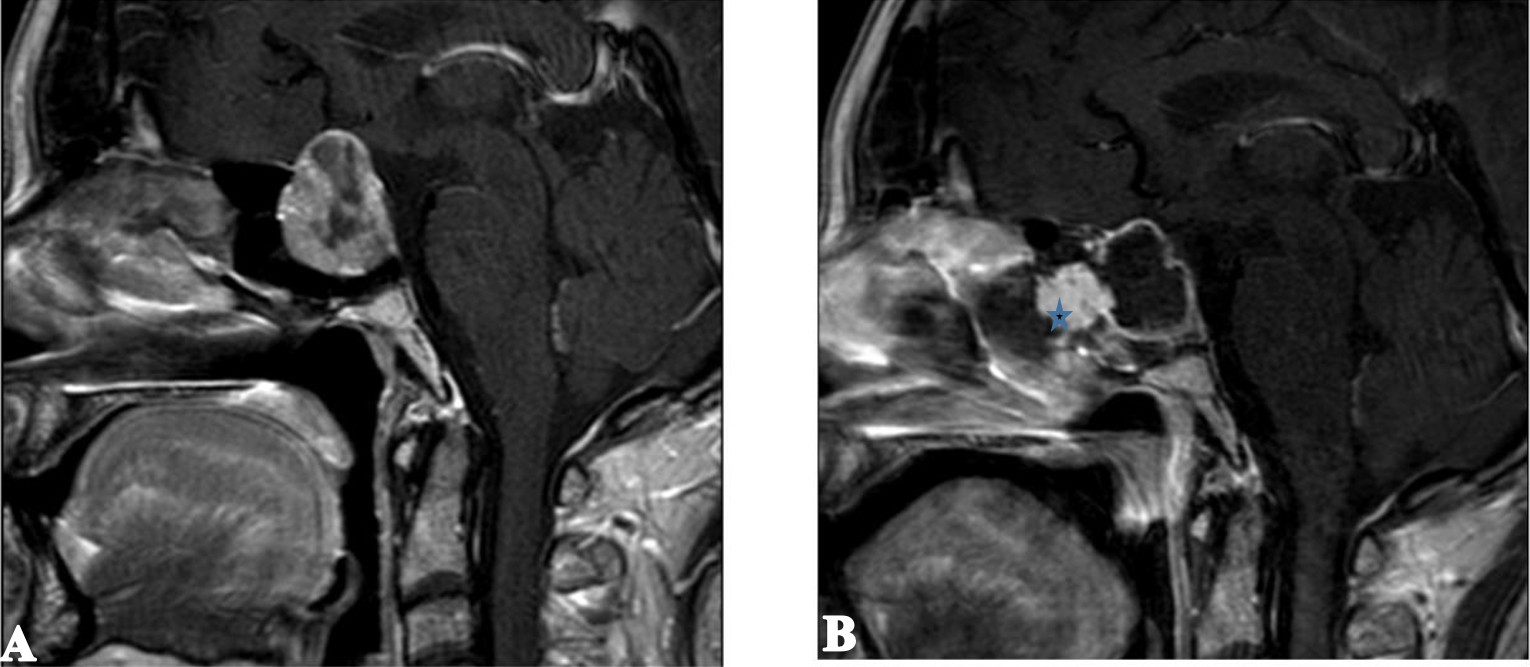

Bu çalışmaya toplam 204 hasta dahil edildi. Hastaların yaş ortalaması 47,3 ± 13,9 yıl olup, geniş bir yaş dağılımı mevcuttu. Olguların 120’si (%58,8) kadın, 84’ü (%41,2) erkekti. Patolojik değerlendirmede en sık saptanan tümör tipi Cushing hastalığı (%20,1) idi. Bunu sırasıyla non-fonksiyonel hipofiz adenomları (%19,6), FSH-LH sekresyonlu adenomlar (%16,7) ve akromegali (%14,2) izledi. Daha az sıklıkta izlenen patolojiler arasında izole hormon salgılayan adenomlar ve nadir hipofizer lezyonlar yer aldı. Postoperatif dönemde diabetes insipidus gelişmesi nedeniyle 70 hastada (%34,3) desmopressin tedavisi gerekli oldu. Bu hastaların 4’ünde (%5,7) uzun dönem takiplerinde desmopressin ihtiyacının devam etmesi nedeniyle kalıcı diabetes insipidus olarak tanımlanmıştır. Geçici diabetes insipidus, postoperatif erken dönemde sık gözlenen komplikasyonlardan biri olarak kaydedildi. Rinore, 30 hastada (%14,7) izlenmiş olup, bu olguların 22’si klinik ve radyolojik olarak BOS fistülü ile uyumlu bulunarak reoperasyona alındı. Reoperasyon sırasında uygulanan onarım yöntemleri heterojenlik göstermekteydi. Bu olguların 14’ünde yağ grefti ile birlikte lomber drenaj, 7’sinde yalnız yağ grefti, 3’ünde yalnız lomber drenaj kullanıldı (Şekil 1). Beş olguda herhangi bir greft veya drenaj uygulanmazken, bir olguda otojen kemik grefti tercih edildi. Rezidüel adenom saptanan hastaların tedavi yaklaşımları incelendiğinde, 4 hastaya ek endoskopik cerrahi, 6 hastaya ise transkranyal cerrahi uygulandığı görüldü. Bu hastalar, rezidüel lezyonun lokalizasyonu ve yayılım özelliklerine göre değerlendirilerek tedavi edildi. Postoperatif hematom, 8 hastada (%3,9) izlendi (Şekil 2). Bu olguların iki tanesinde vasküler yaralanma gelişmesi üzerine endovasküler tedavi uygulanması gerekti. Diğer postoperatif komplikasyonlar arasında epistaksis (n=4, %2), menenjit (n=5, %2,4) ve hidrosefali (n=2, %1) yer aldı. Tüm olgular değerlendirildiğinde mortalite oranı %0,5 olup, bir hasta postoperatif dönemde kaybedildi. Demografik özellikler, patolojik tanı dağılımı ve postoperatif komplikasyonlara ait bulgular Tablo 1’de özetlenmiştir.